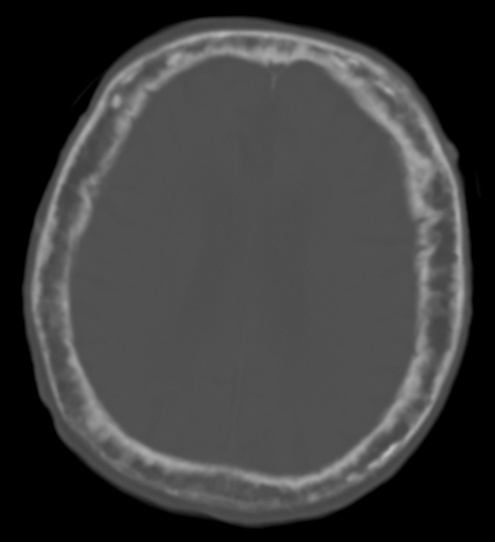

Osteopetrosis

Osteopetrosis is due to a hereditary deficiency in bone resorption.

Osteopetrosis causes abnormally thick, heavy bone that is brittle and easily fractures.

Multiple genetic variants exist, and carbonic anhydrase mutation leads to loss of the acidic microenvironment required for bone resorption.

Clinical features of osteopetrosis include:

- Bone fractures

- Anemia

- Thrombocytopenia

- Leukopenia

- Extramedullary hematopoiesis due to bony replacement of the marrow space

Impingement on cranial nerves due to bony overgrowth may cause characteristic neurologic symptoms based on the cranial nerves that are affected.

Osteopetrosis most often causes vision and hearing loss.

Treatment of osteopetrosis is bone marrow transplant since osteoclasts are derived from monocytes.